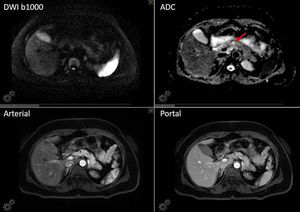

High-resolution MR Imaging of the pancreas. Figure shows a pancreas' cyst (red arrow), which is characterized by free diffusion (low signal on b1000 and high signal on corresponding ADC map) and no contrast uptake. Also note the T2 shine through effect in the gallbladder. Images courtesy of Christos Tsiotsios